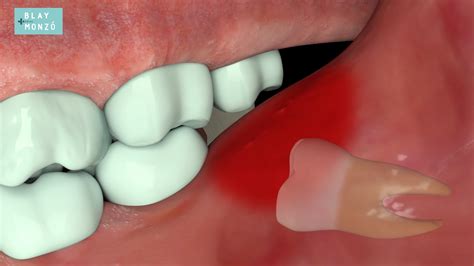

Identificar si tu muela del juicio está causando problemas es esencial para evitar complicaciones mayores. No todas las personas presentan síntomas, pero cuando los hay, suelen ser bastante claros. Presta atención a las siguientes señales:

• Dolor persistente en la parte posterior de la boca o en la mandíbula.

• Inflamación o enrojecimiento de las encías alrededor del diente.

• Mal aliento (halitosis) persistente o un sabor desagradable al morder.

• Dificultad para abrir la boca completamente.

• Dolor de cabeza o dolor que se irradia hacia el oído.

Dejar una muela del juicio que causa problemas sin tratar puede derivar en condiciones más serias. La falta de higiene en esa zona, debido a la dificultad para llegar con el cepillo, favorece la acumulación de bacterias, lo que puede causar:

• Pericoronaritis: Una infección en el tejido de la encía que rodea al diente parcialmente erupcionado.